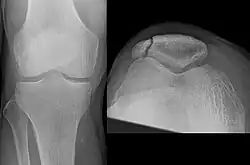

| A fracture of the patella seen on a lateral view | |